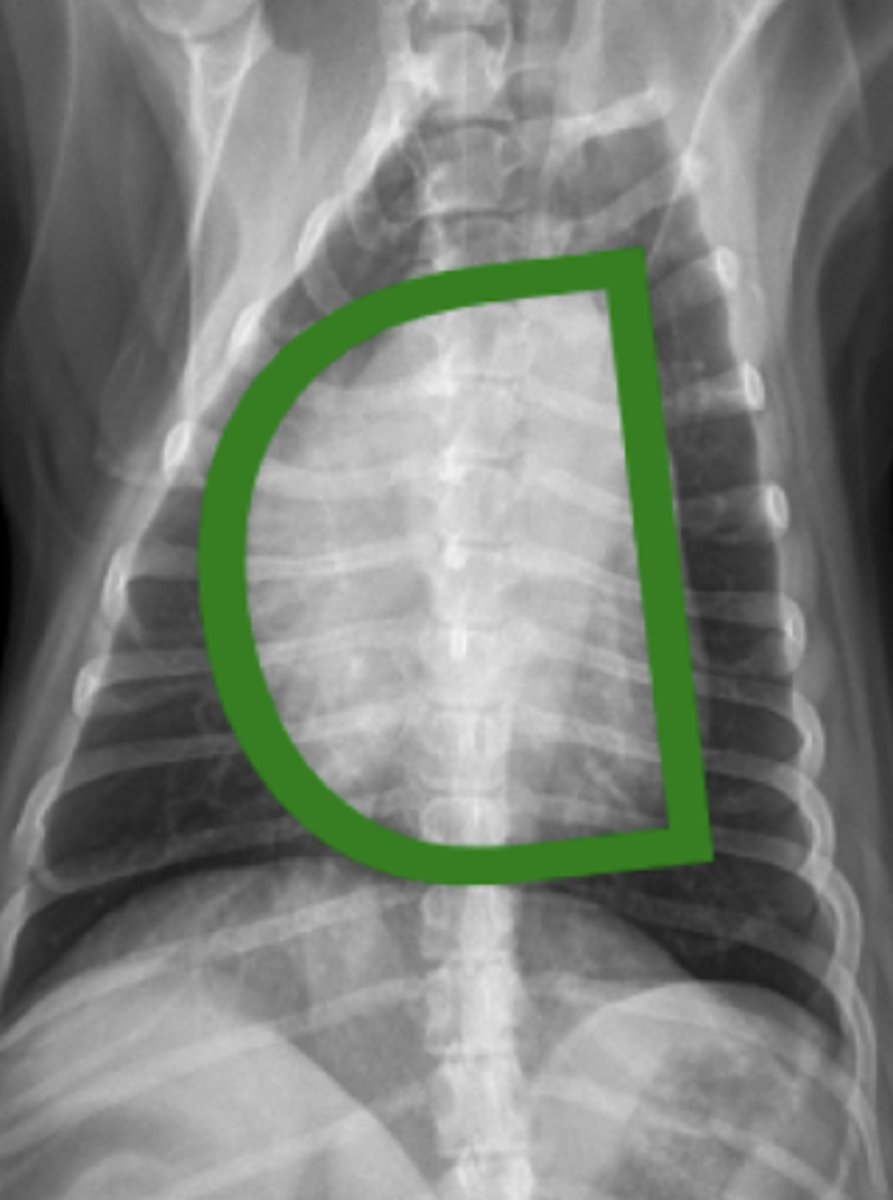

torsión esplénica

(C invertida)

patología: